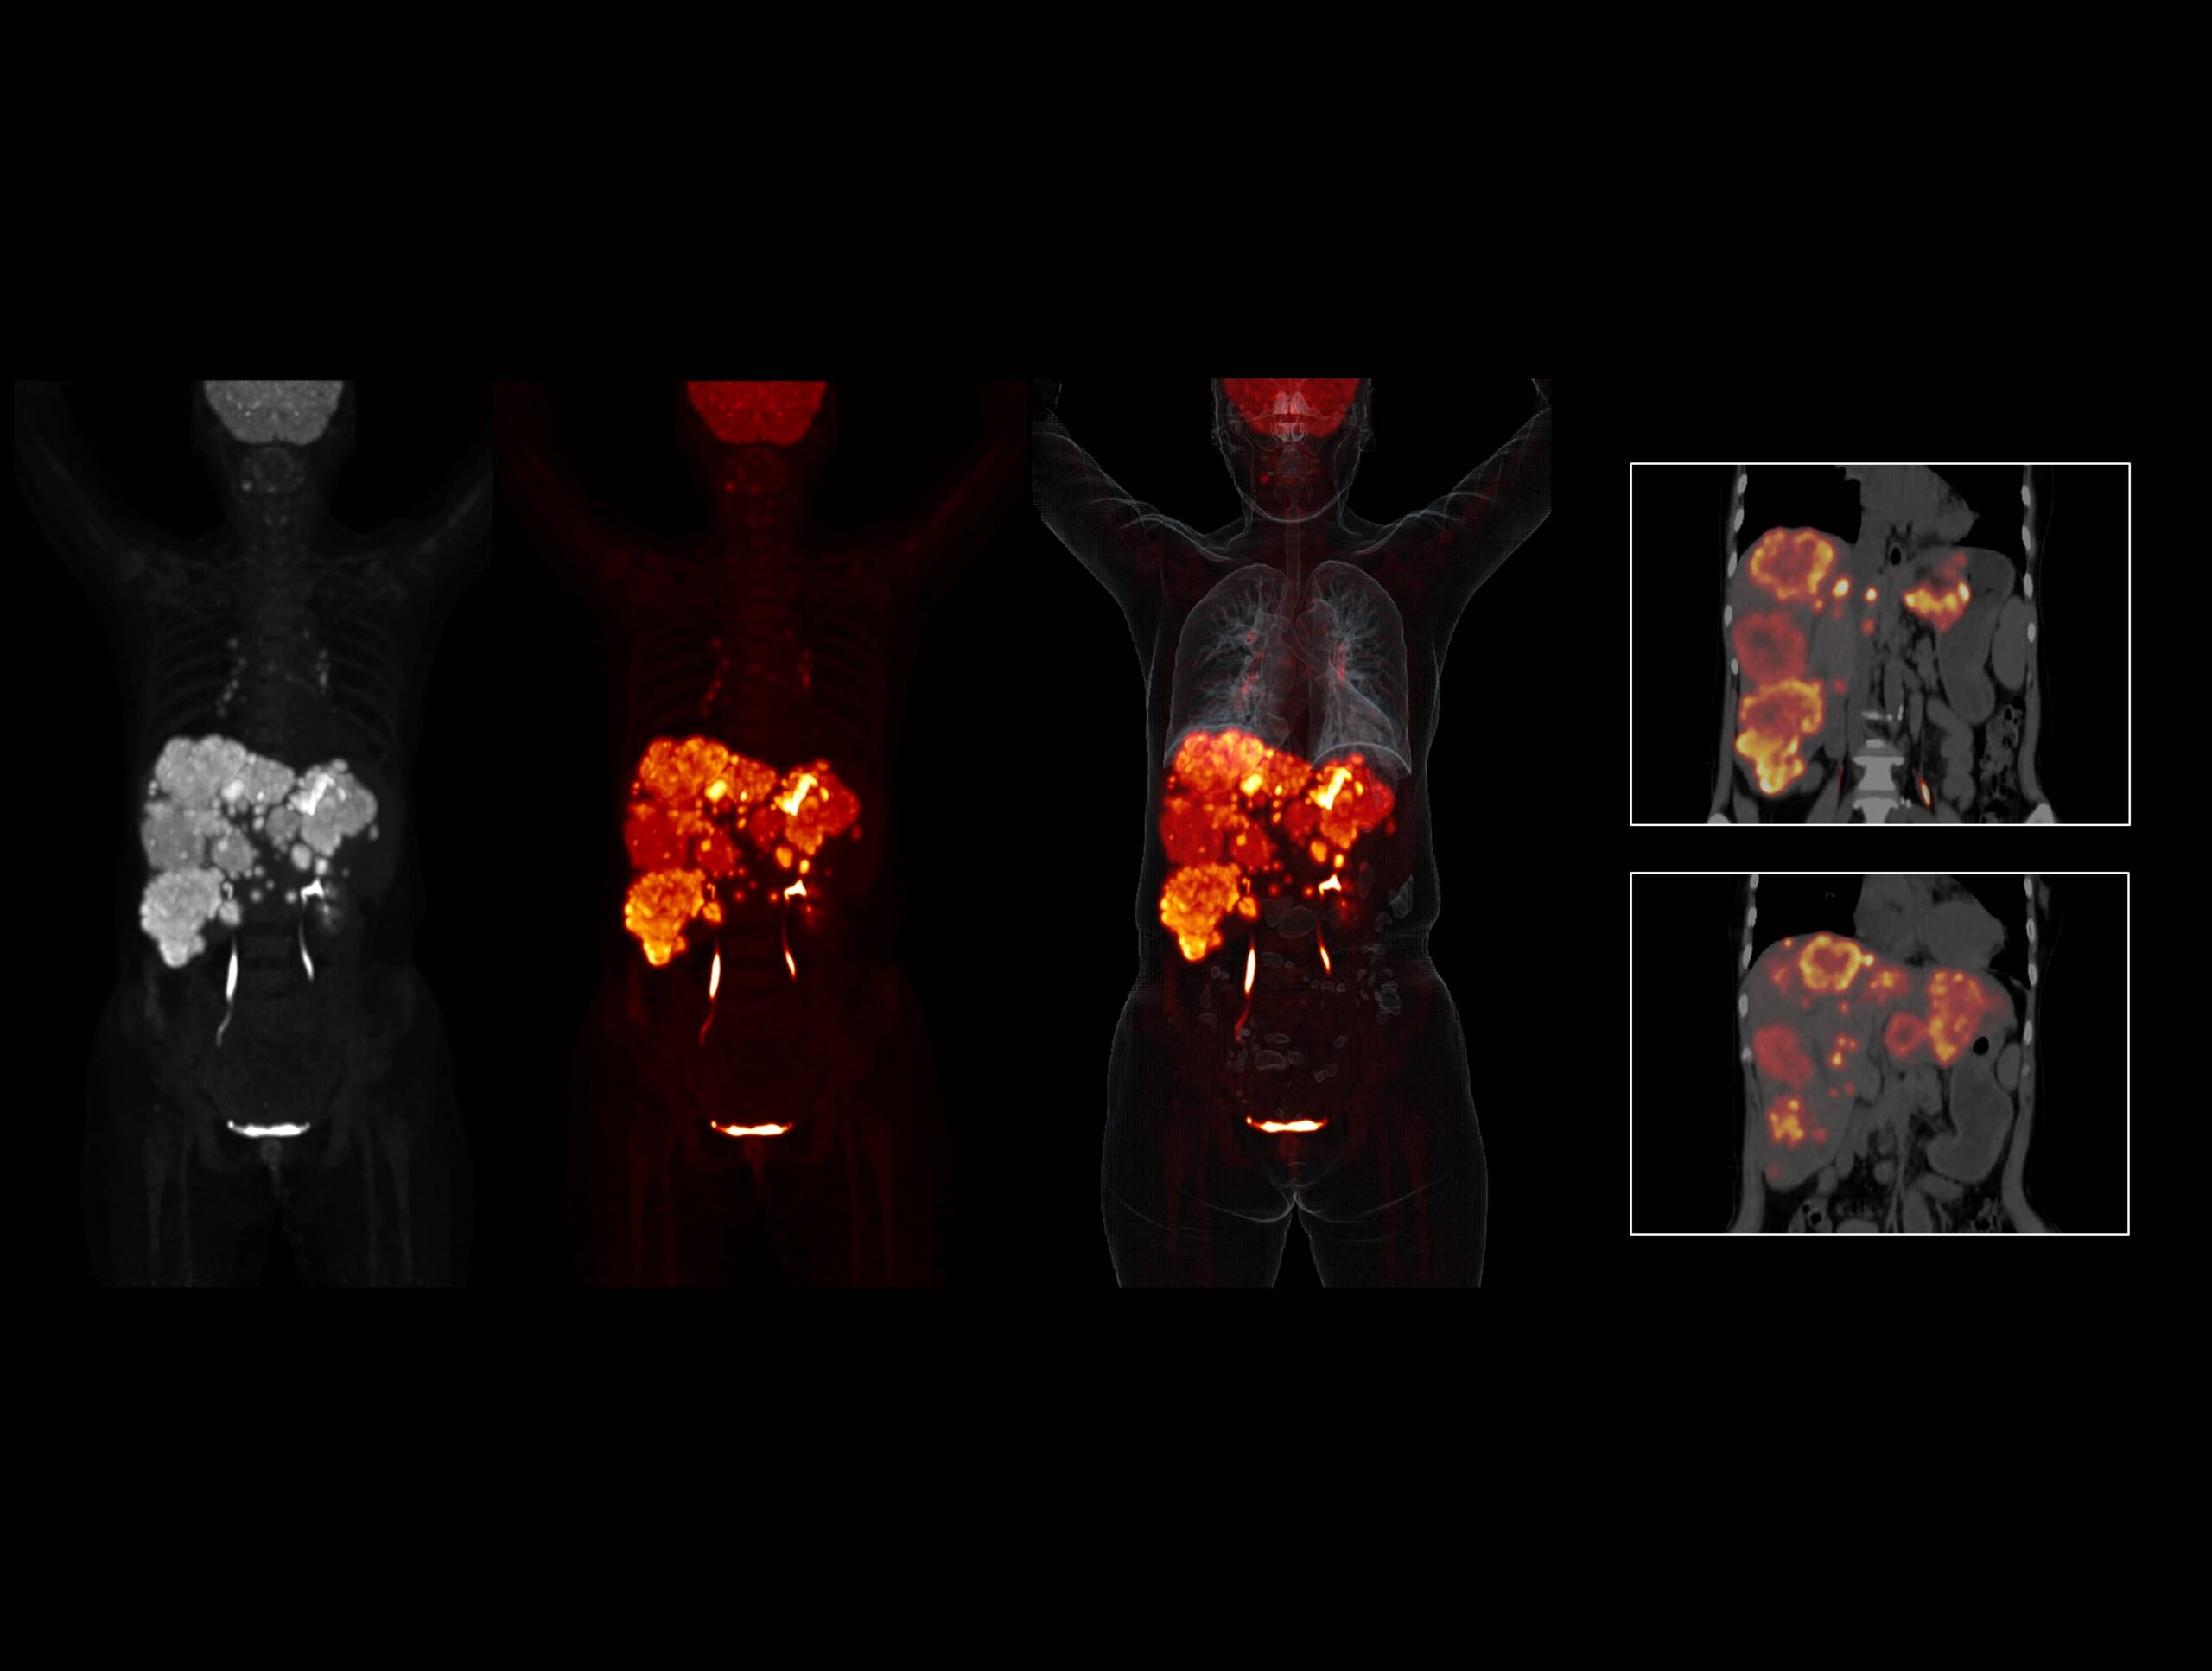

OncoFocus evidențiază clar leziunile hepatice și gastrice

Sistemul high-resolution cu performanță TOF de 189 ps oferă imagini excepționale pentru afecțiuni peritoneale și omentale

Tehnologia Time of Flight îmbunătățește vizibilitatea cu contrast ridicat a leziunilor pulmonare mici

Metastazele extinse ale cancerului de sân sunt dezvăluite clar de sistemul high-resolution cu TOF ultra-rapid